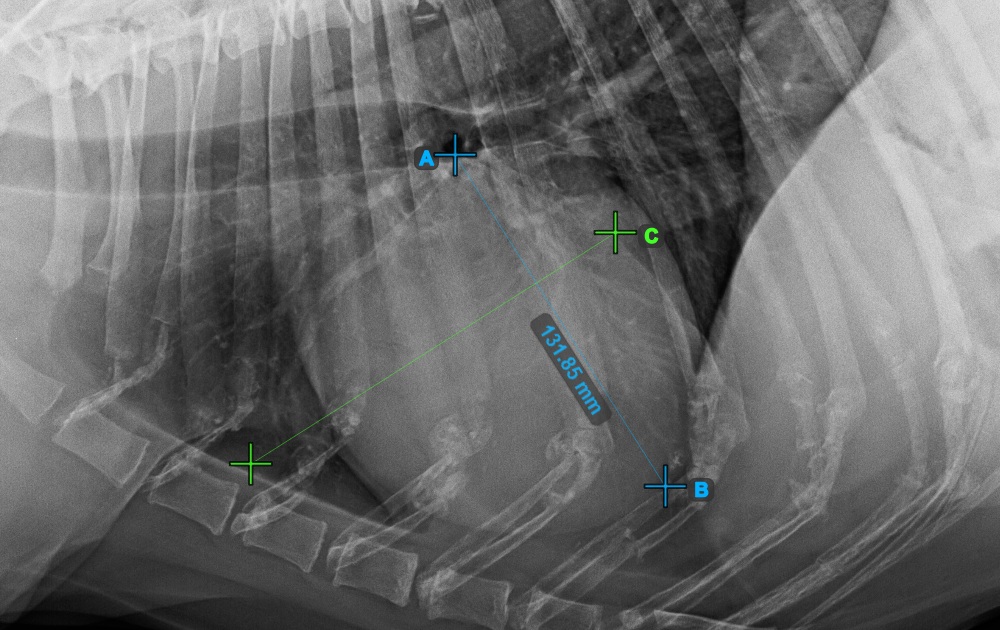

Complete the short axis of the heart by marking the widest left (caudal) point.

The image below represents the typical placement of the most caudal point on the short axis of the heart.